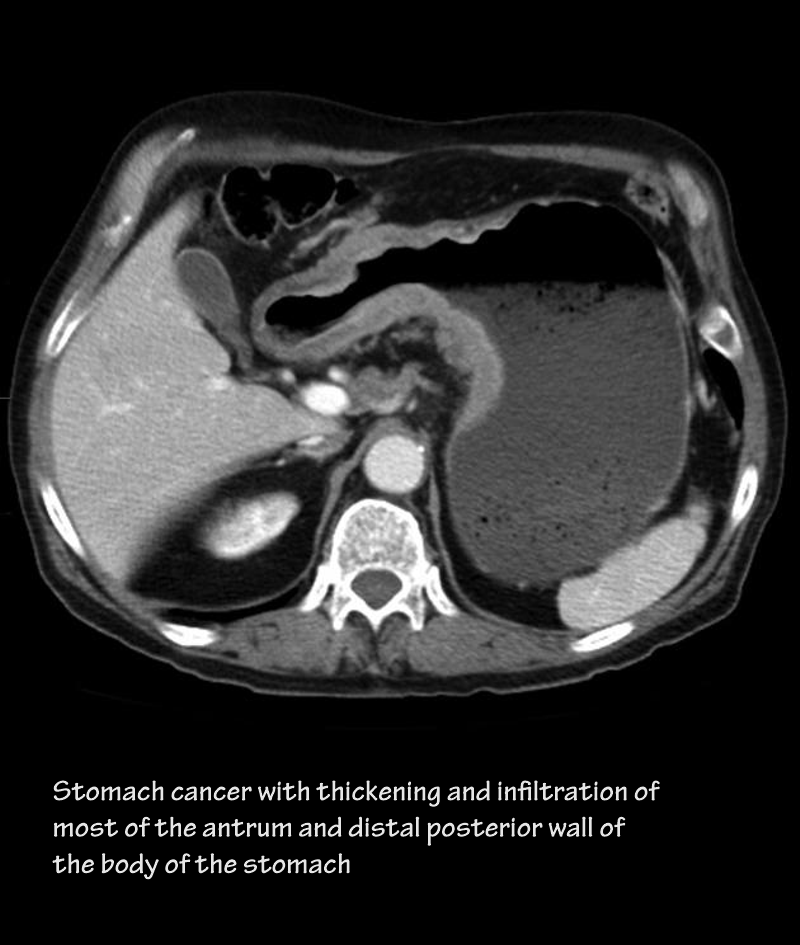

49yo male with abdominal pain and vomiting.

Gastric Outlet Obstruction

• Patient had carcinoma of stomach (CT)